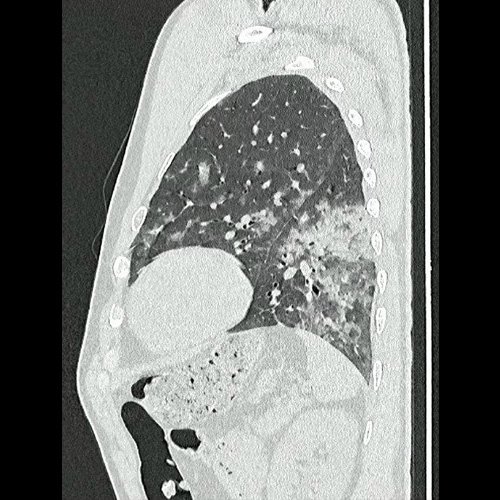

Tomografía de tórax sin contraste endovenosos (Ventana pulmonar- corte sagital)

• Tomografía de tórax sin contraste endovenoso (Dia 0):Se observan múltiples áreas de consolidación parenquimatosa con broncograma aéreo y de distribución difusa por ambos pulmones, predominando en los lóbulos inferiores, asociadas a engrosamiento de los septos y rodeadas de tenue vidrio esmerilado. Se identifican estructuras ganglionares lateroaórticas, pretraqueales y subcarinales, ninguna de ellas sin alcanzar rango megálico.